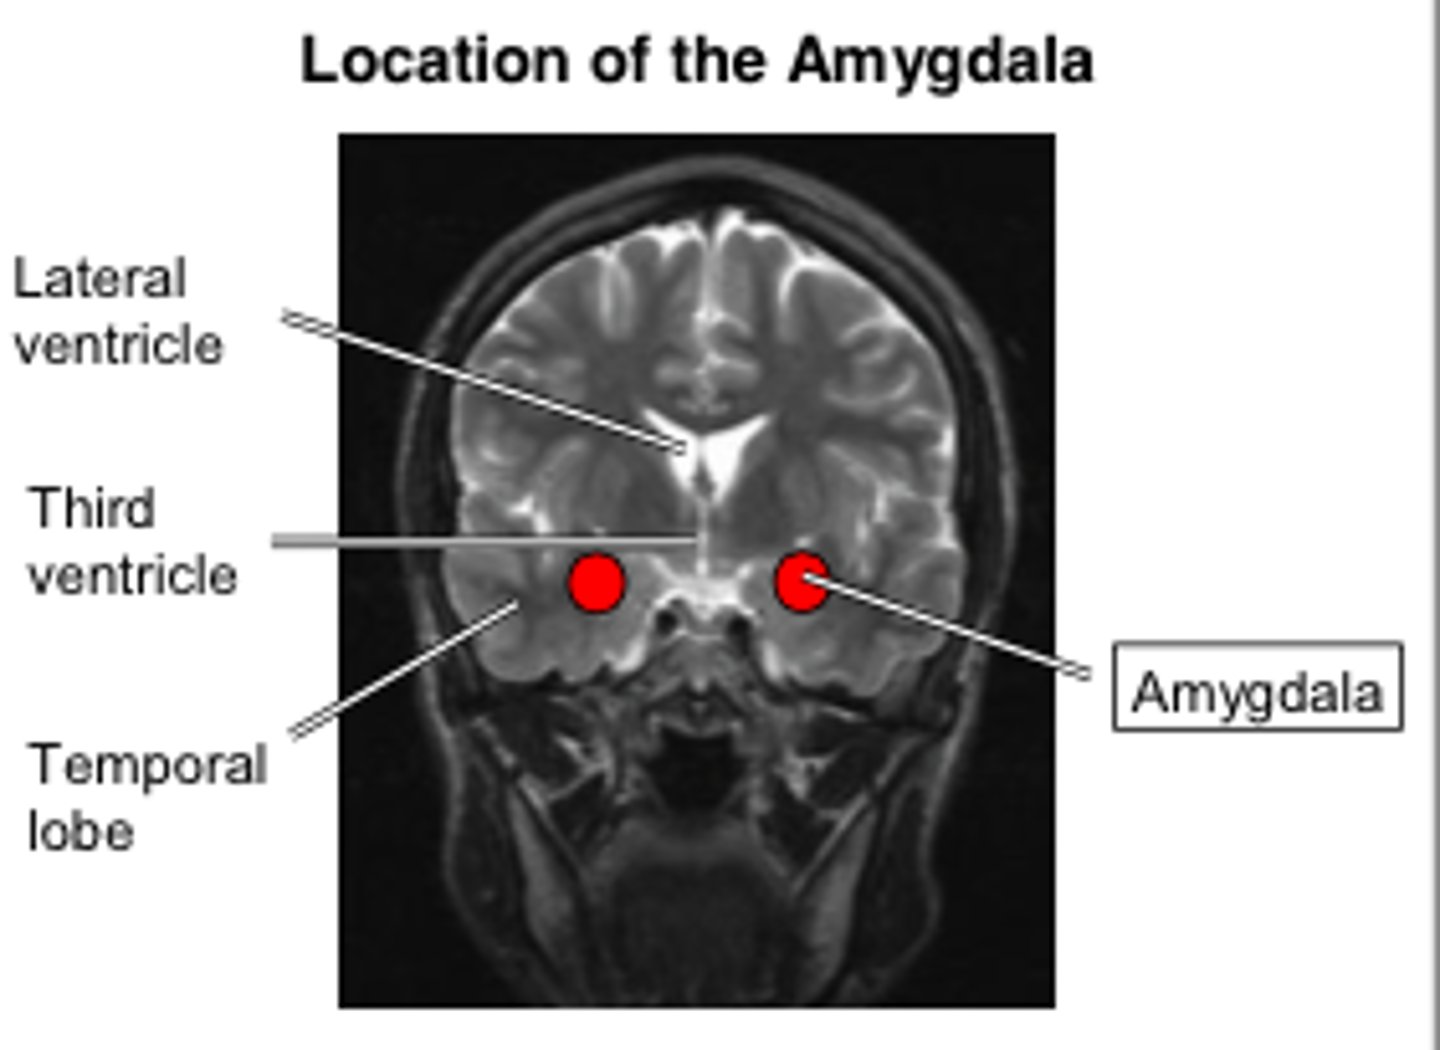

Hyperphagia, hyper-sexuality, hyperorality, hyperdocility

Kluver-Bucy Syndrome

(bilateral amygdala lesion)